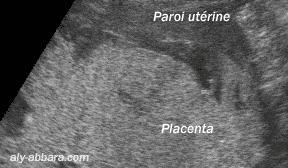

Placenta d'une grossesse à 32 semaines d'aménorrhée

Unité d'échanges materno-placentaire :

Une chambre villositaire limitée en haut par la paroi de l'utérus et en bas par la face

maternelle du placenta puis le flux sanguin circulant à l'intérieur de la chambre.